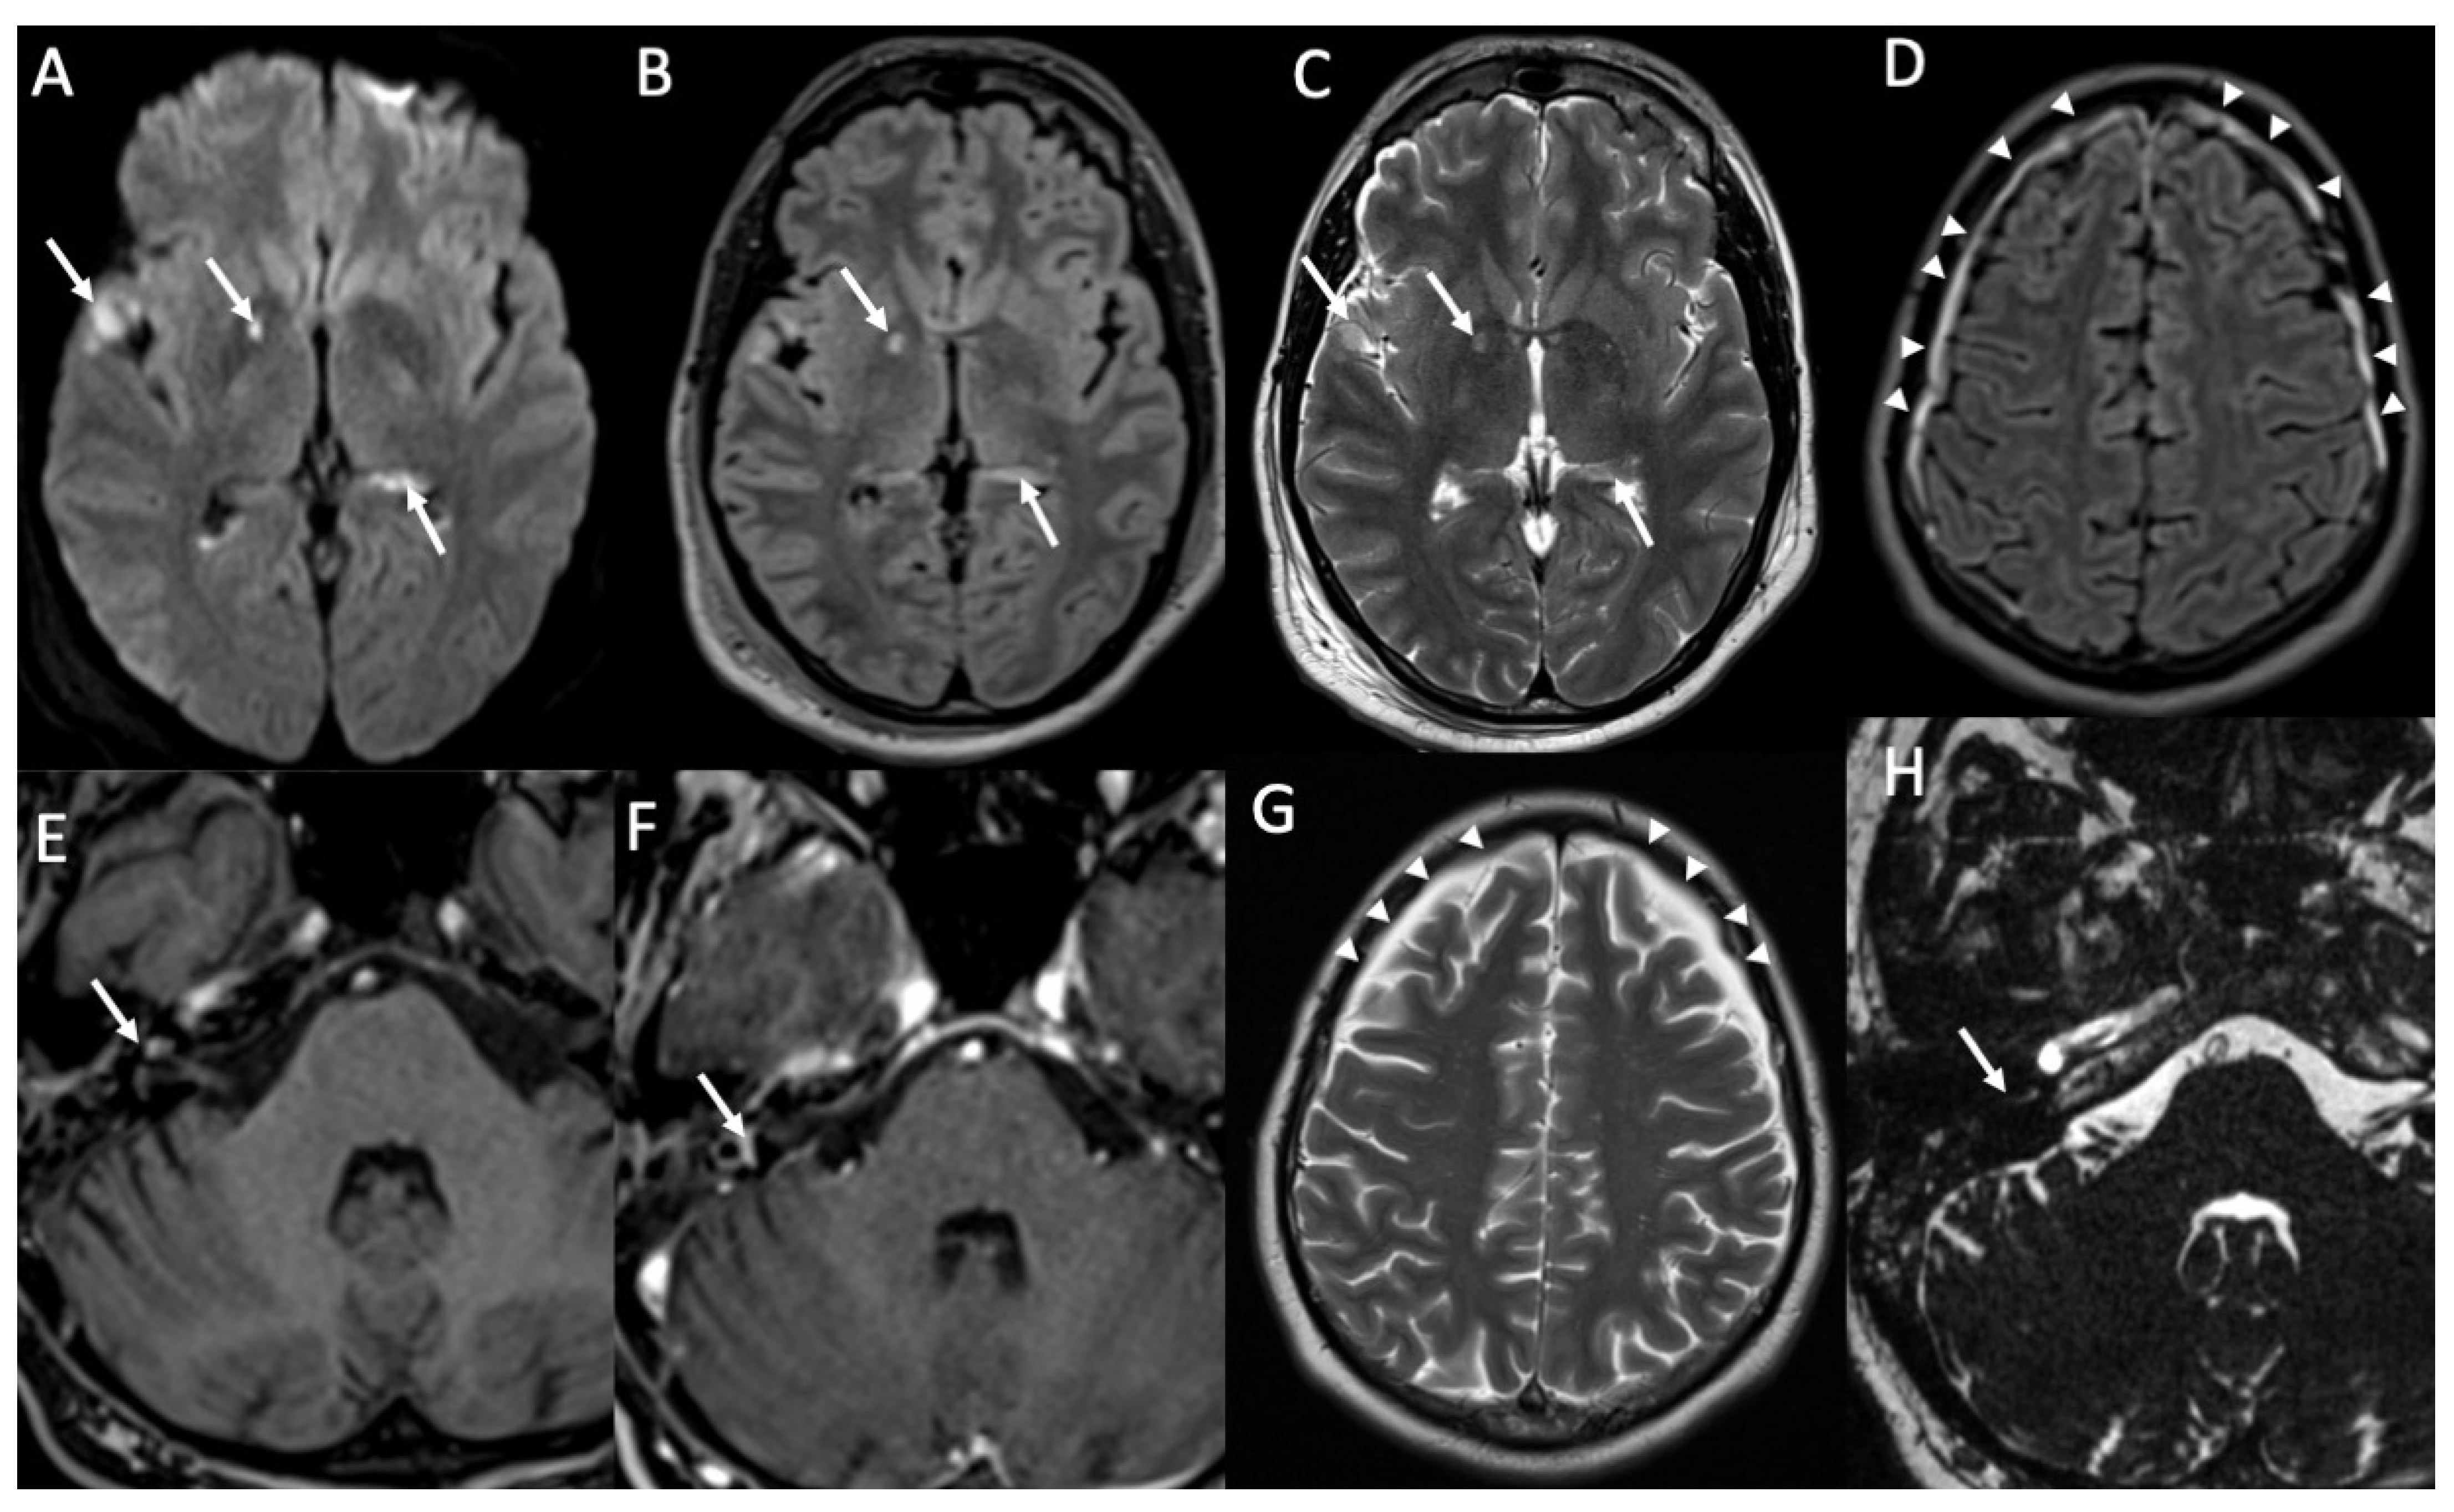

Figure 6.

Axial DWI (A), FLAIR (B), T2 (C,G), enhanced FLAIR (D), T1 with fat-suppression (E), enhanced T1 with fat-suppression (F) and axial 3D-CISS show multiple recent ischemic lesions (arrows in A–C) and pachymenangeal enhancement (arrowheads in D) in a patient with Streptococcus pneumoniae meningitis. There is also cochlear hemorrhage on the right side (arrow in E), with enhancement of the structures of the inner ear (arrow in F). Axial T2 (G) and 3D-CISS (H) performed after one month depict subdural hygroma in the frontal regions bilaterally (arrowheads in G) and loss of the normal fluid signal of the internal right ear due to ossificans labyrinthitis (arrow in H).